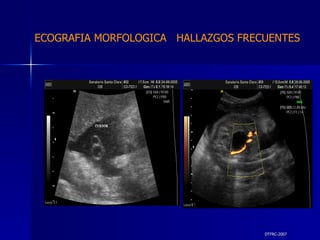

DTFRC-2007 ECOGRAFIA MORFOLOGICA  HALLAZGOS FRECUENTES   MATERIAL Y METODO ES UN ESTUDIO DESCRIPTIVO, RETROSPECTIVO  DE ESTUDIO ECOGRA FICOS REALIZADOS ENTRE MARZO 07 A MARZO 08 EQUIPO DE ALTA RESOLUCION   VOLUSON 730 PRO  MEDISON SA 8000 live MEDISON SA 8000SE CRITERIO DE INCLUSION:   POBLACION GENERAL    GESTACIONES  20 a 24 SEMANAS   UNIVERSO  N 211

DTFRC-2007 ECOGRAFIA MORFOLOGICA  HALLAZGOS FRECUENTES   SISTEMA NERVIOSO CENTRAL TOTAL  8  26 % 1 HIDROCEFALIA 2 VENTRICULO MEGALIA 4 QUISTE DE PLEXO COROIDEO 1 ANENCEFALIA

DTFRC-2007 ECOGRAFIA MORFOLOGICA  HALLAZGOS FRECUENTES   GENITOURINARIA DISPLASIA RENAL MULTIQUISTICA  3 HIDRONEFROSIS  2 QUISTE DE OVARIO FETAL  1 SISTEMA DIGESTIVO DILATACION INTESTINAL  2  SISTEMA ESQUELETICO   PIE BOT  2  20 % 6 % 6 %